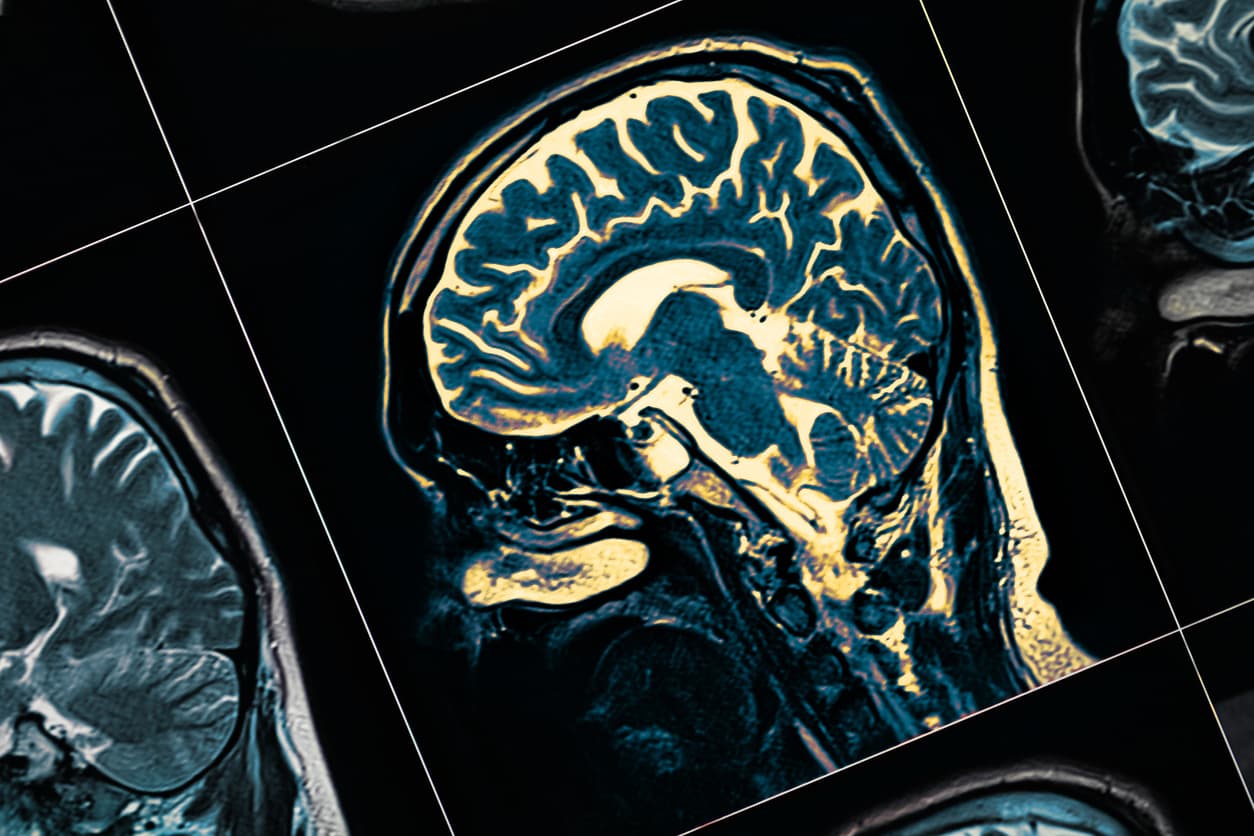

El Alzheimer es un síndrome progresivo que provoca el atrofiamiento del cerebro y la muerte de las neuronas. De acuerdo con Mayo Clinic, es la causa más común de demencia, por lo que también afecta el comportamiento y las habilidades sociales de una persona.